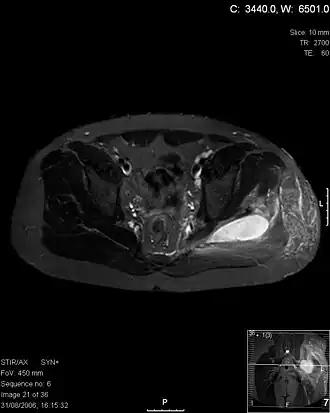

Transversale T2 MRI ter hoogte van de heup laat abcessen zien bij een pyomyositis-patiënt.

Pyomyositis, ook wel tropische pyomyositis of myositis tropicans, is een bacteriële infectie van de skeletspieren die resulteert in met pus gevuld abces. Pyomyositis komt vooral voor in tropische streken maar kan zich ook in gematigde streken voordoen.